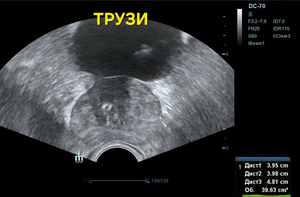

Всё бы ничего, но только на ТРУЗИ объём простаты несколько превышен — 39,6см³, а в периферической зоне справа округлый т. н. атипичный узел диаметром 11,0 мм со слабым кровотоком (фото 1 — 3); а по статистике именно в этой зоне выявляется до 70% рака.

Фото 1 — ТРУЗИ